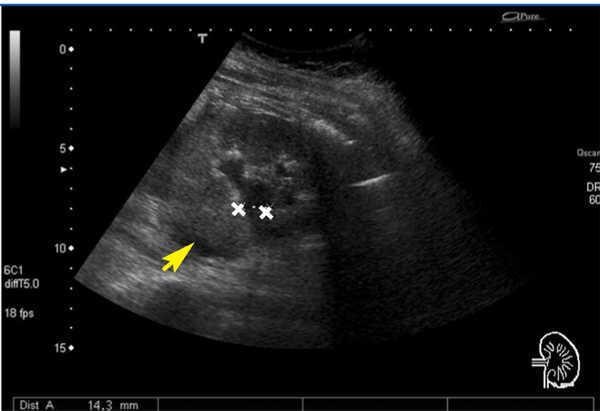

A renal ultrasound revealed grade II-III/IV pelvicalyceal dilatation of the left kidney and fluid collection in the left perirenal space (Figure 2). The patient was gestating with a live foetus. The urology department was advised of the situation, and they placed a left double J ureteral catheter, making passage through a left ureterolithiasis, resulting in the flow of urine with a purulent aspect. We later started treatment with antibiotics and intravenous potassium and bicarbonate, achieving clinical improvement. Based on the clinical symptoms, the previous laboratory analyses, and the current values, the patient was diagnosed with RTA.

Figure 2. Left renal ultrasound